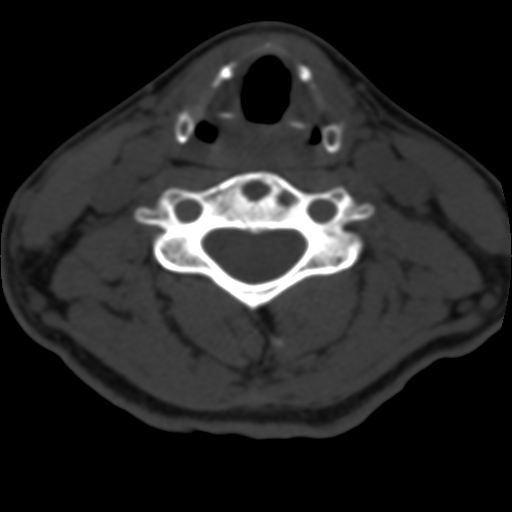

女,34岁,颈部外伤六天,伤后颈部疼痛。ct扫描:c4椎体见两个圆形低密度影,边缘见硬化,其余椎体及椎间盘未见异常。请教各位c4椎体为何病变?

考虑c4椎体许莫尔氏结节

软骨岛

许莫氏结节

许莫氏结节是髓核突出至上下椎体内形成软骨下结节。无特效药物能中止本病的进展,但综合性的治疗措施在减轻疼痛,保护关节功能方面还是比较满意的。治疗方面首先要让患者对本病有所认识,知道如何保护关节,避免对关节的过度压力;肥胖者要减肥;纠正不正的姿势;在病情稳定期进行适当的锻炼以延缓关节的退行性变化,在有疼痛症状时应予受累关节以充分的休息及应用药物或其他治疗措施

许莫氏结节经部发生的还没见过。暂不考虑。考虑发育异常。

首先可以肯定的是该病灶与外伤无关,次则良性骨肿瘤或肿瘤样病变基本可以明确。

软骨岛--系长骨或扁骨骨化过程中局限性骨化障碍而残留的软骨组织。多见于股骨颈,边界清楚,通常单发,可长达1ocm。大多为圆形透亮影,并可见有邻近重叠或跨越的骨纹。

骨囊肿极少发生于颈椎。青少年外伤后出现颈椎不适,应予以重视,行x线片检查,发现颈椎骨透亮度较强、膨胀程度较轻、无骨膜反应的囊肿,应考虑本病的可能。

脊柱嗜酸性肉芽肿以单发居多,骨质破坏早期可呈轻度膨胀,其内可见骨嵴,边缘清楚或硬化,亦可单纯溶骨性破坏,边缘不规则。

我首先考虑:第4颈椎椎体骨囊肿。